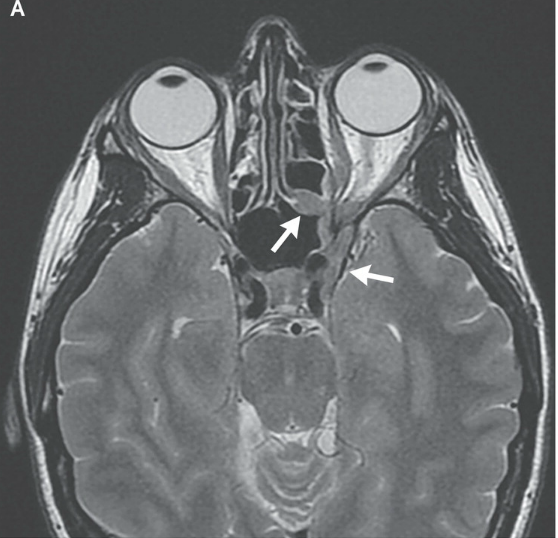

RMN de cráneo mostró tejido blando anormal a lo largo de las paredes anterior y lateral del seno esfenoidal izquierdo, en el vértice de la órbita izquierda extendiéndose posteriormente en el seno cavernoso izquierdo. Este tejido blando era de densidad intermedia tanto en una imagen potenciada en T2 (Figura A) Y una imagen potenciada en T1 con contraste (Figura 1B). Una imagen de RMN con contraste, coronal (Figura 1C) mostró aumento anormal en la unión del seno cavernoso y la cavum de Meckel en el lado izquierdo, con realce de tejido que se extendía a la parte interna del foramen oval.

Figura 1

Estudios por imágenes de los senos paranasales y órbitas.

RMN DE ÓRBITAS REALIZADA EN OTRO HOSPITAL. Una imagen en T2 (Panel A)y una T1 con contraste (Panel B) muestra tejido de densidad intermedia tapizando el seno esfenoidal y afectando el vértice de la órbita izquierda y el seno cavernoso (flechas). Un corte coronal en T1 (Panel C) muestra realce de partes blandas extendiéndose inferiormente al foramen oval. Una TC de órbita (Panel D) muestra que el hueso entre el seno esfenoidal y el vértice de la órbita están relativamente intactos a pesar de la presencia de tejido con densidad de partes blandas anormal a ambos lados (flecha).

TC de las órbitas (Figura 1D) reveló que el hueso entre el tejido blando anormal en el seno esfenoidal izquierdo y el tejido blando anormal en el vértice de la órbita izquierda estaba prácticamente intacto.